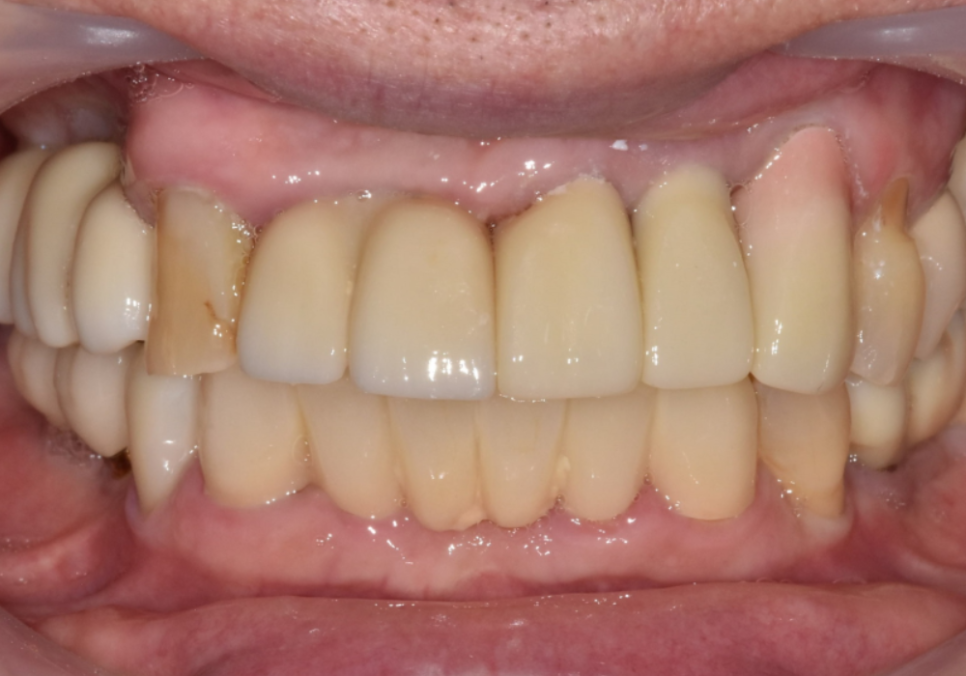

심미성을 위한 최종 보철물

음식물 끼임, 거뭇한 무언가 보인다면?

임플란트가 뼈와 단단히 붙기를

3개월간 기다린 후,

드디어 최종 보철물을 만드는 날이 왔습니다.

사실 앞니는 심미성이 생명이라

의사 입장에도 매 순간이 참 조심스러운데요.

특히 잇몸이 많이 내려간 송곳니(#23)의 경우,

230315

무너진 라인을 무시하고 보철물만 씌우면

치아가 비정상적으로 길어 보여

자칫 인상이 부자연스러워 보일 수 있어요.

이런 형태적 한계를 보완하기 위해

저희는 '핑크 포세린' 기법을 적용했습니다.

231213

보철물 뿌리 쪽을 환자분의

실제 잇몸 색과 유사한 분홍색 도자기로

정교하게 제작하는 방식이죠.

덕분에 건강한 잇몸이 다시 차오른 듯한

자연스러운 라인을 완성해 드릴 수 있었습니다.

230315(전) 231213 (후)

230315 (전) 231213 (후)